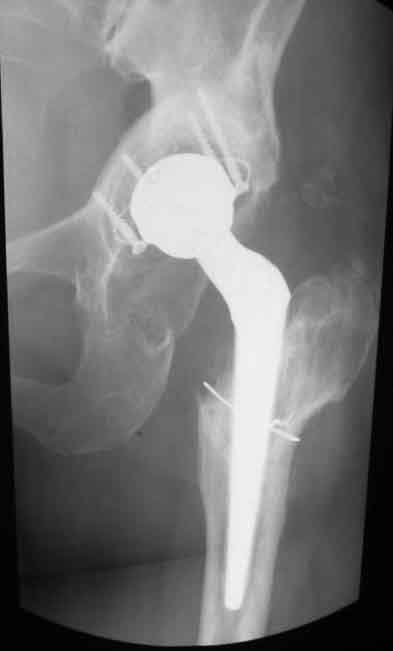

Уважаемые коллеги. Хотелось бы услышать мнения и советы по представляемому случаю. Пациентка 45 лет. Бесцементное эндопротезирование левого тазобедренного сустава 6 лет назад (впадина RM, Mathys, металл-металл, ножка Зульцеровская). За 10 лет до протезирования – коррегирующая остеотомия бедренной кости, которая не срослась в течение года до удаления пластины, а затем срослась в течение 3 месяцев иммобилизации в кокситной повязке. После протезирования получилось наблюдать пациентку почти постоянно, поскольку через 2 года синтезировал ей лодыжки на оперированной стороне, затем, через несколько месяцев удалил фиксаторы, а в 2009г. резецировал мениск на противоположной стороне. Боли все эти годы не беспокоили. Пациентка чуть выше среднего роста, вес тела нормальный. Физические нагрузки переносила хорошо. Работает на 7 этаже без лифта. Год назад экстирпация матки по поводу лейомиомы больших размеров. Несколько месяцев назад появились боли в области левого тазобедренного сустава. При рентгеновском и КТ исследованиях (июль с.г.) – нестабильность тазового компонента. От предложенной замены протеза пациентка на тот момент, слава богу, отказалась. Через какое то время боли в области левого тазобедренного сустава практически полностью прошли, а около 2 месяцев назад появилось ощущение патологической подвижности таза и боли в паху справа, которые через некоторое время уменьшились, а потом снова усилились после значительных физических нагрузок (много ходила по песку на пляже, носила тяжести). Ежедневно принимала диклофенак. На рентгенограммах – переломы правой лонной кости. Сейчас госпитализирована из-за болей в паху справа. Боли слева не беспокоят. На фоне снижения нагрузок в стационаре боли значимо уменьшились. Способна ходить без средств дополнительной опоры.В анализах крови чуть повышены трансаминазы и гамма-ГТ, моча без особенностей.

Вопросы: -правильно ли я расцениваю переломы как стрессовые на фоне неполноценного таза (pelvic insufficiency stress fractures)? -Можно ли так же расценить ситуацию на стороне протеза и, соответственно, не торопиться с ревизией, рассчитывая на вторичную стабилизацию? Уж больно не хочется менять ножку. -Если думать о ревизии, то когда? На представленных снимках тазобедренный сустав до и сразу после операции, затем 2 снимка 2009г., когда ничего не беспокоило, затем КТ 2-х месячной давности и вчерашние рентгенограммы обоих тазобедренных суставов.